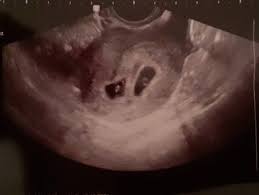

Ab wann kann man im ultraschall erkennen, ob man eineiige oder zweieiige zwillinge bekommt? Kann man von dem auch iwelsche hilfe gebrauchen/beantragen? Hallo ich würde gerne wissen ab wann man beim ultraschall erkennen kann ob es zwillinge werden und ob es vorher schon zu erkennen ist z.b wenn sich keins versteckt kann man es sehen sobald man die fruchthöhle sieht (oder eben dann zwei) oder wenn man eine/zwei embyonalanlagen sieht. Hallo 8baby8, in der 8.ssw (7+2) könnte man eine zweite fruchthöhle erkennen. Für die meisten frauen, die keine fruchtbarkeitsbehandlung hatten.

Bei einer kinderwunschbehandlung kannst du davon ausgehen, dass deine babys zweieiig sind. Wann kann man kindergeld, elterngeld beantragen? Wann kann man per ultraschall das geschlecht erkennen? Im ultraschall kann man meist auch sehr gut erkennen, ob es sich um eineiige (monozygote) oder zweieiige (dizygote) zwillinge handelt. Innerhalb des ersten schwangerschaftsdrittels stellt sich heraus, ob sie zwei während einer ultraschalluntersuchung kann der arzt oder die ärztin schon erkennen, ob es sich um eineiige oder zweieiige zwillinge handelt. Kann ich dabei das geschlecht meines kindes erfahren? Man erkennt zwillinge schon, sobald die herzaktionen im ultraschall erkennbar sind. Um eine übersicht über solche themen sowie wichtige. Für die meisten frauen, die keine fruchtbarkeitsbehandlung hatten. Behandelt man zwillinge anders als andere geschwister? Ab wann kann man die arbeit mit jungen pferden beginnen? Ich würde mir eine 2. Wann kann man schwanger werden?

Im ultraschall kann man meist auch sehr gut erkennen, ob es sich um eineiige (monozygote) oder zweieiige (dizygote) zwillinge handelt.